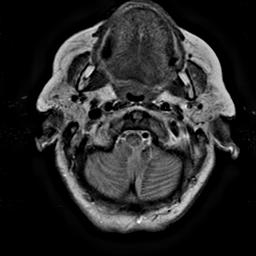

To demonstrate the effectiveness and efficiency of the proposed image fusion method , we conduct a set of comparative experiments on three image datasets. The first is composed by 8 pairs of multi-modal medical images and the second one contains 15 pairs of multi-focus gray or color natural images. These two datasets are often used in many related papers and some examples are shown in Figure 3(a) and Figure 3(b). The third one is a new multi-focus cervical cell image dataset collected by ourselves, which consists of 15 groups of color images and each group contains a series of multi-focus cervix cell images with size of or , etc. Some source examples are shown in Figure 3(c). Our source code implemented in C++ along with the new multi-focus cervical cell image dataset is available online.

We first evaluate the performance of the proposed method under varying total number of octaves and number of layers sampled per octave. The fused images of a pair of multi-modal medical images with different and are shown in Figure 4. In this example, on the one hand, when only 1 or 2 octaves are involved in constructing the DoG pyramid, the fused images fail to keep the integrity information of large size objects (e.g. eyeballs), while by increasing the value of , the integrity information of eyeballs is preserved. On the other hand, although not as significant as the increase of octave numbers , the fused image can contain more details by the increase of layer numbers . The corresponding objective quality metrics are shown in Figure 5. As shown in Figure 5(a), most of the metric values are improved as the number of octaves increases with the fixed layer numbers 3 in the global tendency and each of them tends to be stable when the number of octaves is 5. To get a relatively good quality from Figure 5(b), we can notice that some of the metric values can get a good performance when the number of layers is 3, such as the MI, SSIM, QI and VIF, though there are only a little change of all the metric values by increasing the number of layers with the fixed octave numbers 5. Because it will result in more computation burden with the increase of the value and , and for different kinds of source images, there are different performance with the diverse parameter settings. To get a trade-off between them in our experiments, we set for the multi-modal dataset, for the natural datasets and for the multi-focus cell dataset, respectively.

Figure 6 shows the fused images obtained by different methods with the multi-modal source images shown in Figure 3(a). As shown in these figures, the proposed method can produce images which preserve the complementary information of different source images well. Moreover, due to the scale-invariant structure saliency selection, our method can keep the integrity information of large size objects and the visual details simultaneously. Although the fused image generated by other methods can also capture the details to some extent, all of them fail to keep the integrity information of large size objects such as the eyeballs. Furthermore, from Figure 6(k)-6(t), the DTCWT, GFF, IM and NSCT methods may decrease the brightness and contrast while the proposed method can preserve these features and details without producing visible artifacts and brightness distortions.